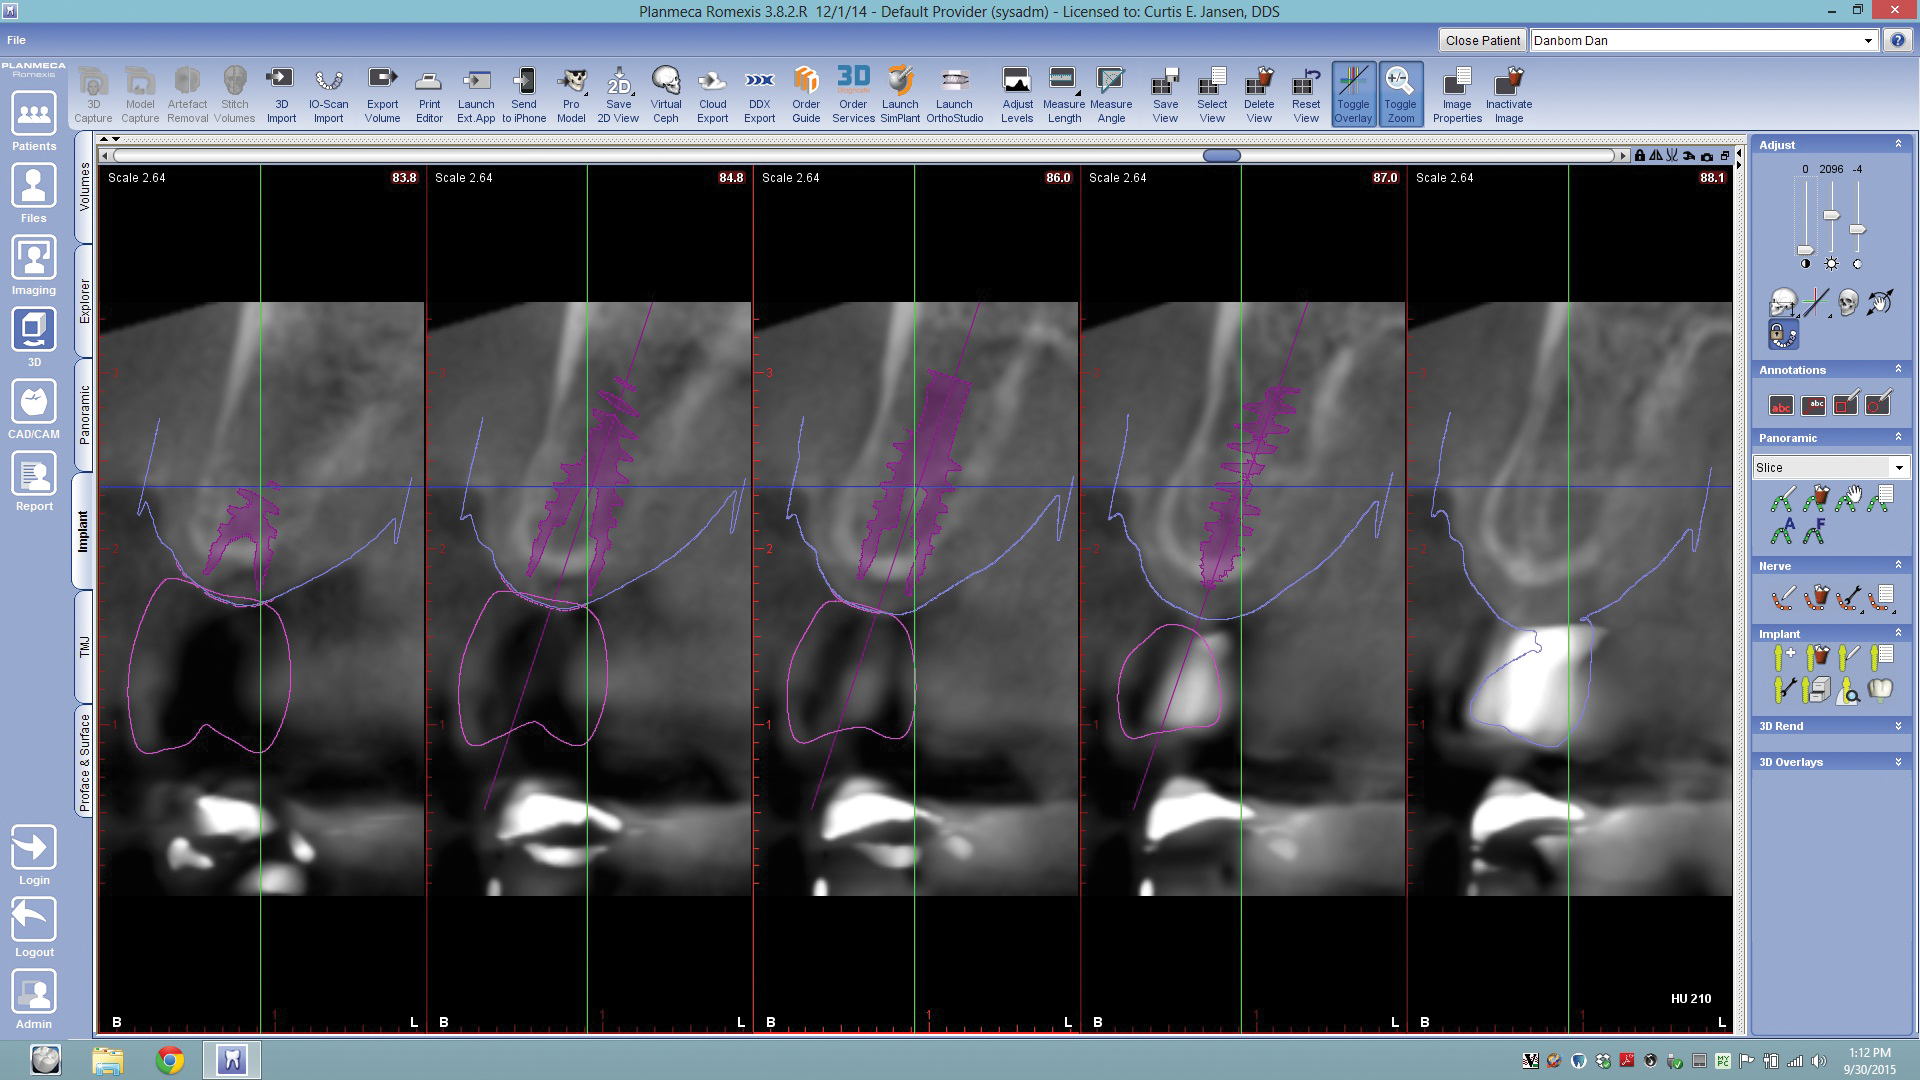

In this workflow model, intraoral images are captured using the IOS, after which computer software evaluates and manipulates the images into 3-D renderings, such as digital images of the impression and digital models. The dentist then uses this information to design the proposed restoration—a computer-aided design, or CAD, process (Figure 1 through Figure 3). Once the restoration is designed, the information is transferred to the in-office milling unit for fabrication.

Fig 1. Whether in the dental office or the laboratory, CAD enables efficient and accurate design and evaluation of proposed restorations based on IOS data: multiple restorations can be done with CAD at one time (Fig 1), and individual cusps (Fig 2) can be manipulated and put in occlusion, as can contacts and restoration profiles (Fig 3).

Figure 1

Fig 9. By merging CBCT files with IOS files and using implant planning software, dental professionals can plan all components of the implant/restoration procedure in advance for a restoratively driven approach: CBCT, IOS, and CAD merged and overlayed as one (Fig 9); implant placement and implant guide CAD (Fig 10).

Figure 9